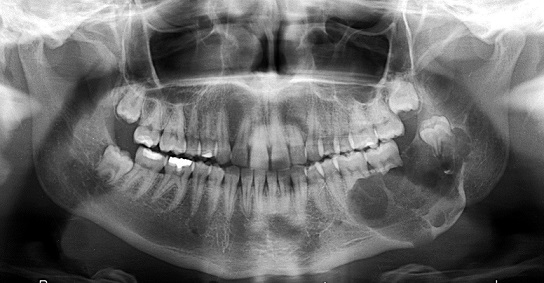

İnkşafı və böyüməsi tədricən baş verdiyindən, bu proses pasiyent tərəfindən demək olar ki hiss edilmir. Yalnız törəmənin ciddi ölçülərə çatması nəticəsində və ya iltihablanması nəticəsində meydana çıxan kliniki əlamətlər nəticəsində aşkarlanır. Əksər hallarda isə çəkilən diş və çənə rentgen şəkillərində təsadüfən rast gəlinir.